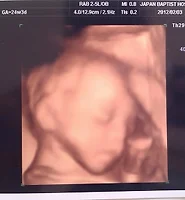

소피도 5월말에 세상 구경하러 나올 예정이라^^